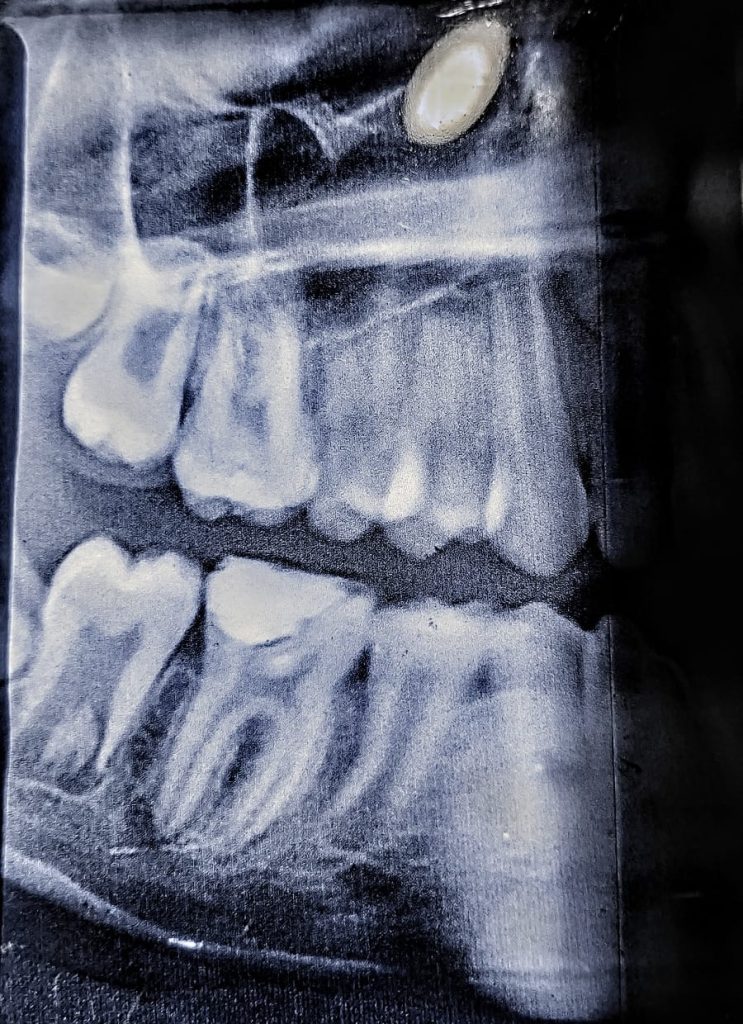

Radiograph:

radiograph shows periapical radiolucency with no apex formation in mesial and distal roots.